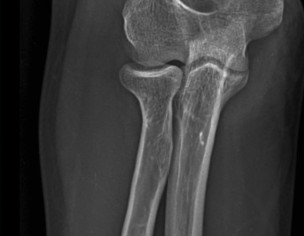

My husband had elbow surgery on 9th of August. I want to know about physiotherapy. When can we start physiotherapy so he can bend and extend his arm freely.Kindly guide us. If we start now will it effect joint or not. TIA